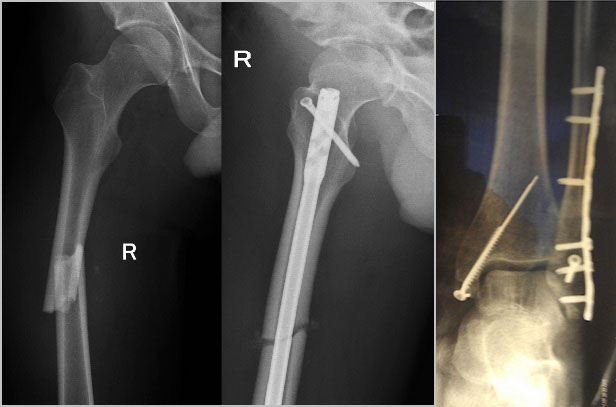

Классификация переломов диафиза бедренной кости: Иллюстрации и информация